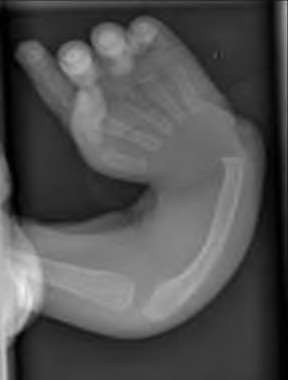

A 20-year-old park ranger trips and falls onto his right wrist with the wrist in extension and pronation. The local urgent care orders both radiographs and a CT, which you review and determine to be normal. The patient complains of ulnar-sided wrist pain. On exam, his tenderness is localized to the fovea. Ulnar deviation also causes him pain. There is no snapping sensation with wrist supination, flexion, and ulnar deviation. He otherwise has 5/5 strength to his first dorsal interosseous muscle with 4mm static two-point discrimination on the ulnar side of the 4th digit. Which of the following injuries is most likely responsible for his symptoms and exam?